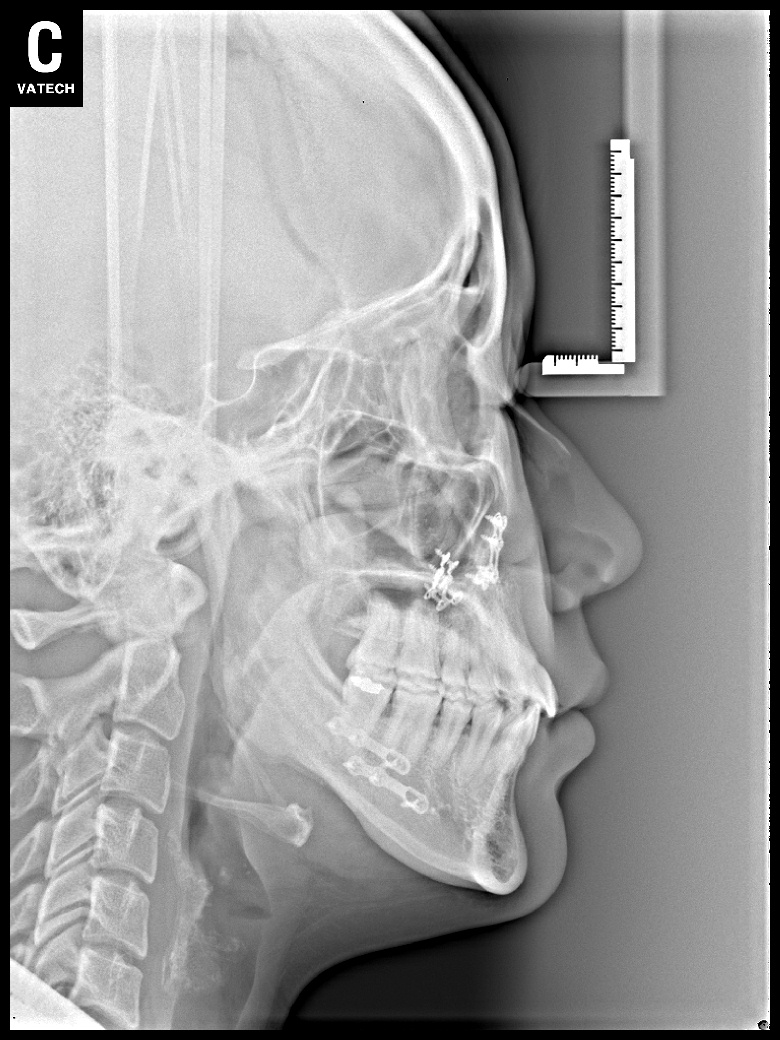

치료 전 사진입니다.